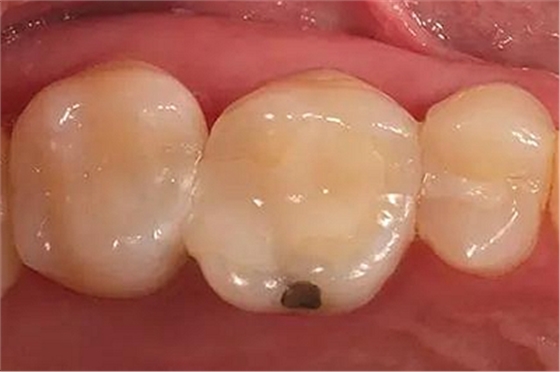

步驟1 原始狀況

16牙位牙齒牙合面觀.

牙齒經(jīng)過根管治療且充填修補(bǔ),需要重新修復(fù)。